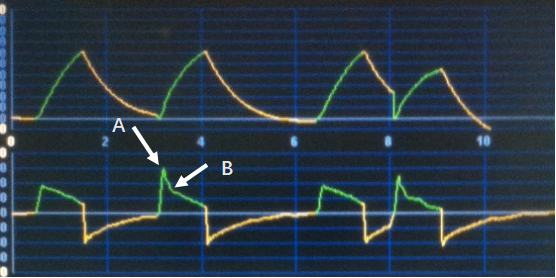

波形的“异常”与自主驱动的有无、出现的时间点和强度密切相关。当控制通气时,呼吸波形形态取决于机械通气的模式、参数设置和患者胸肺呼吸力学状态(见上篇“机械通气波形分析:基础篇”)。当存在自主呼吸驱动时,压力型通气模式决定了患者气道开口处的压力值,呼吸过程中肺内压力则受自主呼吸的影响,驱动越强,肺内压越低,肺内外压力差越大,相应时间点的吸入流量越高(运动方程)(图1-A);容量型模式下如果预设恒定吸气流量,则气道压的高低受自主呼吸的影响,吸气驱动越强,气道压力越低,在极端情况下可见“流量饥饿”现象。总体而言,与完全控制通气时的波形比较,伴随自主驱动的呼吸波形大多会在吸气相或呼气相出现明显的未预料的拐点或趋势(图1-B、C)。

图1 存在自主呼吸驱动的呼吸波形